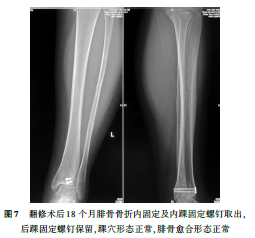

骨远端对合关系及腓骨骨折端复位良好(图6)。术后3d出院休养,定期门诊复查;术后12周取出固定踝穴的1枚螺钉,部分负重练习;术后6个月恢复正常行走;术后18个月腓骨骨折愈合良好,再次手术取出腓骨骨折内固定钛板螺钉及内踝固定螺钉(图7),手术切口愈合后恢复正常活动。术后3年随访,美国矫形外科足踝协会(AOFAS)评分100分。